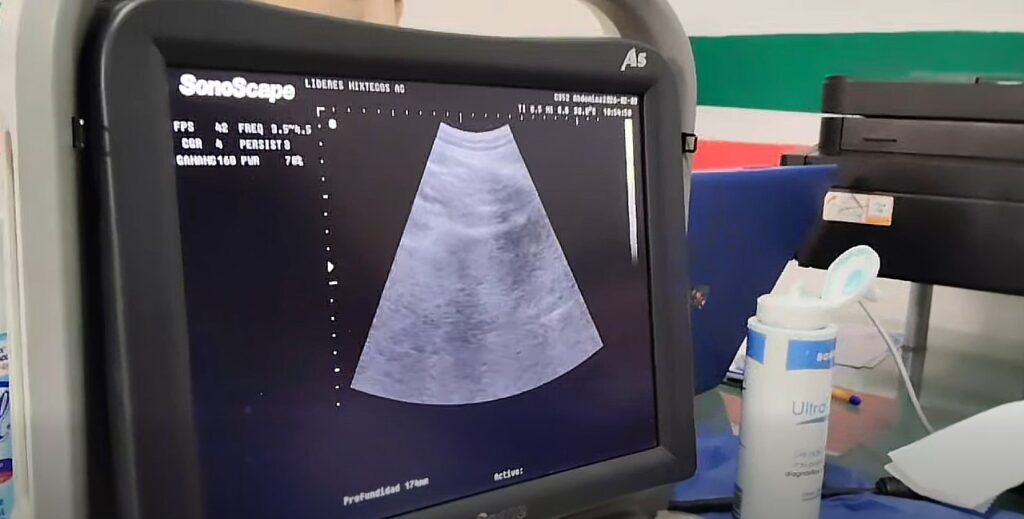

Personal médico realiza ultrasonido gratuito a una paciente durante la Jornada de Ultrasonidos del Ayuntamiento de Huaquechula y el DIF Municipal.

El Ayuntamiento de Huaquechula, a través del DIF Municipal, mantiene en marcha la Jornada de Ultrasonidos Gratuitos, una acción orientada a fortalecer la salud preventiva y garantizar el acceso a estudios médicos sin costo para la población.

Esta iniciativa pone a disposición de la ciudadanía diversos estudios diagnósticos, entre ellos ultrasonidos abdominales, pélvicos y mamarios, así como electrocardiogramas y colposcopias, lo que permite detectar de manera oportuna posibles enfermedades y canalizar a las personas a una atención adecuada.